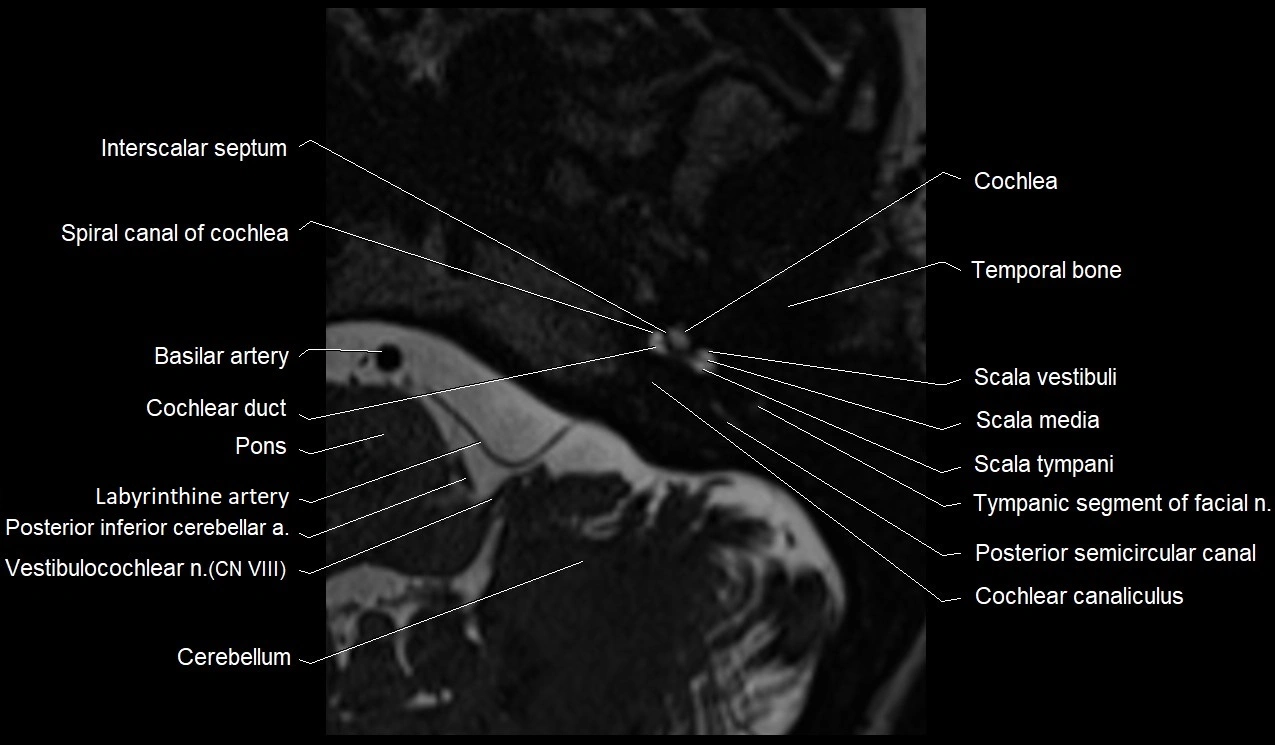

MRI Appearance

• The abducens nerve is a small, thin, linear structure

• Best visualized on high-resolution T2-weighted 3D MRI sequences (e.g., FIESTA or CISS)

• Seen as a hypointense (dark) line running from the brainstem at the pontomedullary junction, traversing the prepontine cistern, and entering Dorello’s canal under the petrosphenoidal ligament, then into the cavernous sinus, and finally the orbit

• May be challenging to visualize in standard MRI due to its small size

• Pathology may be inferred by absence, displacement, or enhancement of the nerve

MRI images

image